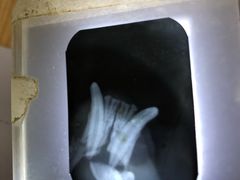

• 北京赛佳动物医院

• -北京赛佳动物医院